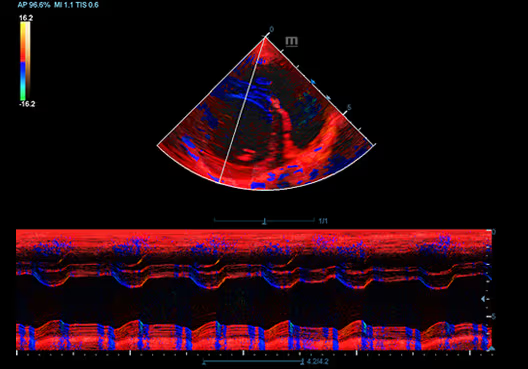

Köpek Kalbinin M Modu Rengi

Köpek Kalbinin M Modu Rengi